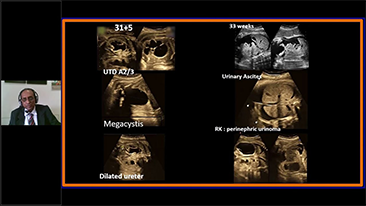

? necessĂĄrio otimizar fluxos de trabalho de obstetrĂcia e ginecologia para suportar grandes volumes na triagem da saĂșde da mulher. Por exemplo, as mĂĄs-forma??es do sistema nervoso central (SNC) s?o uma das anomalias congĂȘnitas mais comuns. Obten??o de imagens ruins devido Ă mĂĄ posi??o fetal, o MSP Ă© particularmente difĂcil de ser encontrado em um ultrassom 2D. Portanto, a detec??o e as medi??es automĂĄticas podem aumentar muito a eficiĂȘncia da realiza??o do exame.